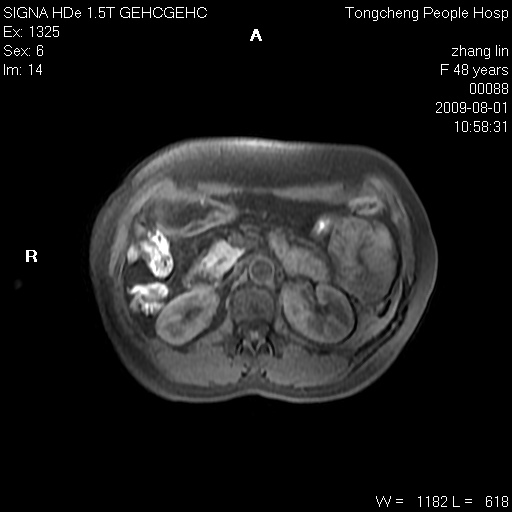

女,48岁。健康体检,彩超发现右肾占位性病变。平素健康。

临床诊断:右肾占位性病变,性质待定(囊肿?肿瘤?)。

上中腹部mr平扫+增强扫描,图像如下:

右肾上极见一类圆形病灶,t1wi呈等信号t2wi呈等高混杂信号,三期增强无强化,边界清---考虑囊肿出血。

同反相位均表现为等信号,病变无强化,考虑含蛋白的囊肿可能,弥散加权相或许有些帮助,